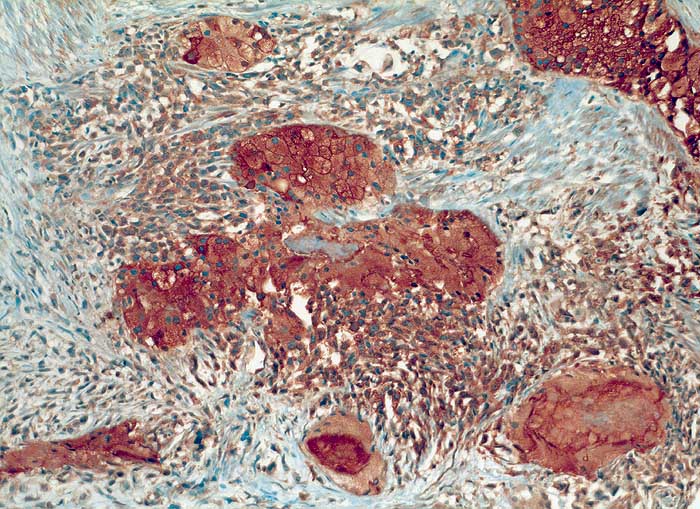

metaplastisches Prostatakarzinom

Sowohl die klarzellige als auch die sarkomatoide Tumorkomponente sind stark PSAP positiv.

Bei den immunhistochemischen Untersuchungen sind die epithelial differenzierten Tumoranteile positiv für den Epithelmarker Lu-5 und für die prostataspezifischen Marker PSA und PSAP. Die sarkomatös differenzierten Anteile sind dagegen Lu-5 negativ, zeigen aber ganz herdförmig eine schwache, aber eindeutige Positivität für PSAP (prostataspezifische saure Phosphatase). Die sarkomatösen Anteile sind ausserdem stark positiv für Vimentin und S-100. Die S-100-Positivität beweist zusammen mit der herdförmigen Ausbildung von chondroider Matrix und dem ausgedehnt myxoiden Hintergrund eine chondrosarkomatöse Differenzierung. Die myogenen Marker Actin, SMA und Desmin sind dagegen negativ bei positiver interner Kontrolle von glatten Muskelfaserbündeln und Gefässen. Der Proliferationsmarker Ki-67 wird in ca. 90% der sarkomatös differenzierten Tumorzellen, dagegen nur etwa in ca. 5% der epithelial differenzierten Anteile exprimiert.

Zusammengefasst handelt es sich hier um einen aussergewöhnlichen und seltenen Fall eines metaplastischen Karzinoms mit heterologen Anteilen (Chondrosarkom). Diese Tumoren machen lediglich ca. 0,1% aller Prostatakarzinome aus. Wie bei diesem Patienten, entwickeln sich etwa die Hälfte dieser Tumoren mit sarkomatöser Differenzierung aus einem gewöhnlichen Adenokarzinom. Die herdförmige Positivität der sarkomatösen Anteile für PSAP deutet auch hier darauf hin, dass diese durch Transformation des Adenokarzinoms entstanden sind. Einige Autoren bevorzugen deshalb auch den Begriff "metaplastisches Karzinom". Es ist denkbar, dass eine allenfalls vorausgegangene Strahlen- oder Hormontherapie bei dieser Transformation eine Rolle gespielt hat. Es handelt sich in der Regel um hoch aggressive Tumoren mit einer ungünstigen Prognose, wofür hier auch die ausserordentlich hohe proliferative Aktivität der sarkomatösen Tumoranteile spricht.

Histologie

Immunhistochemie

PSAP

100